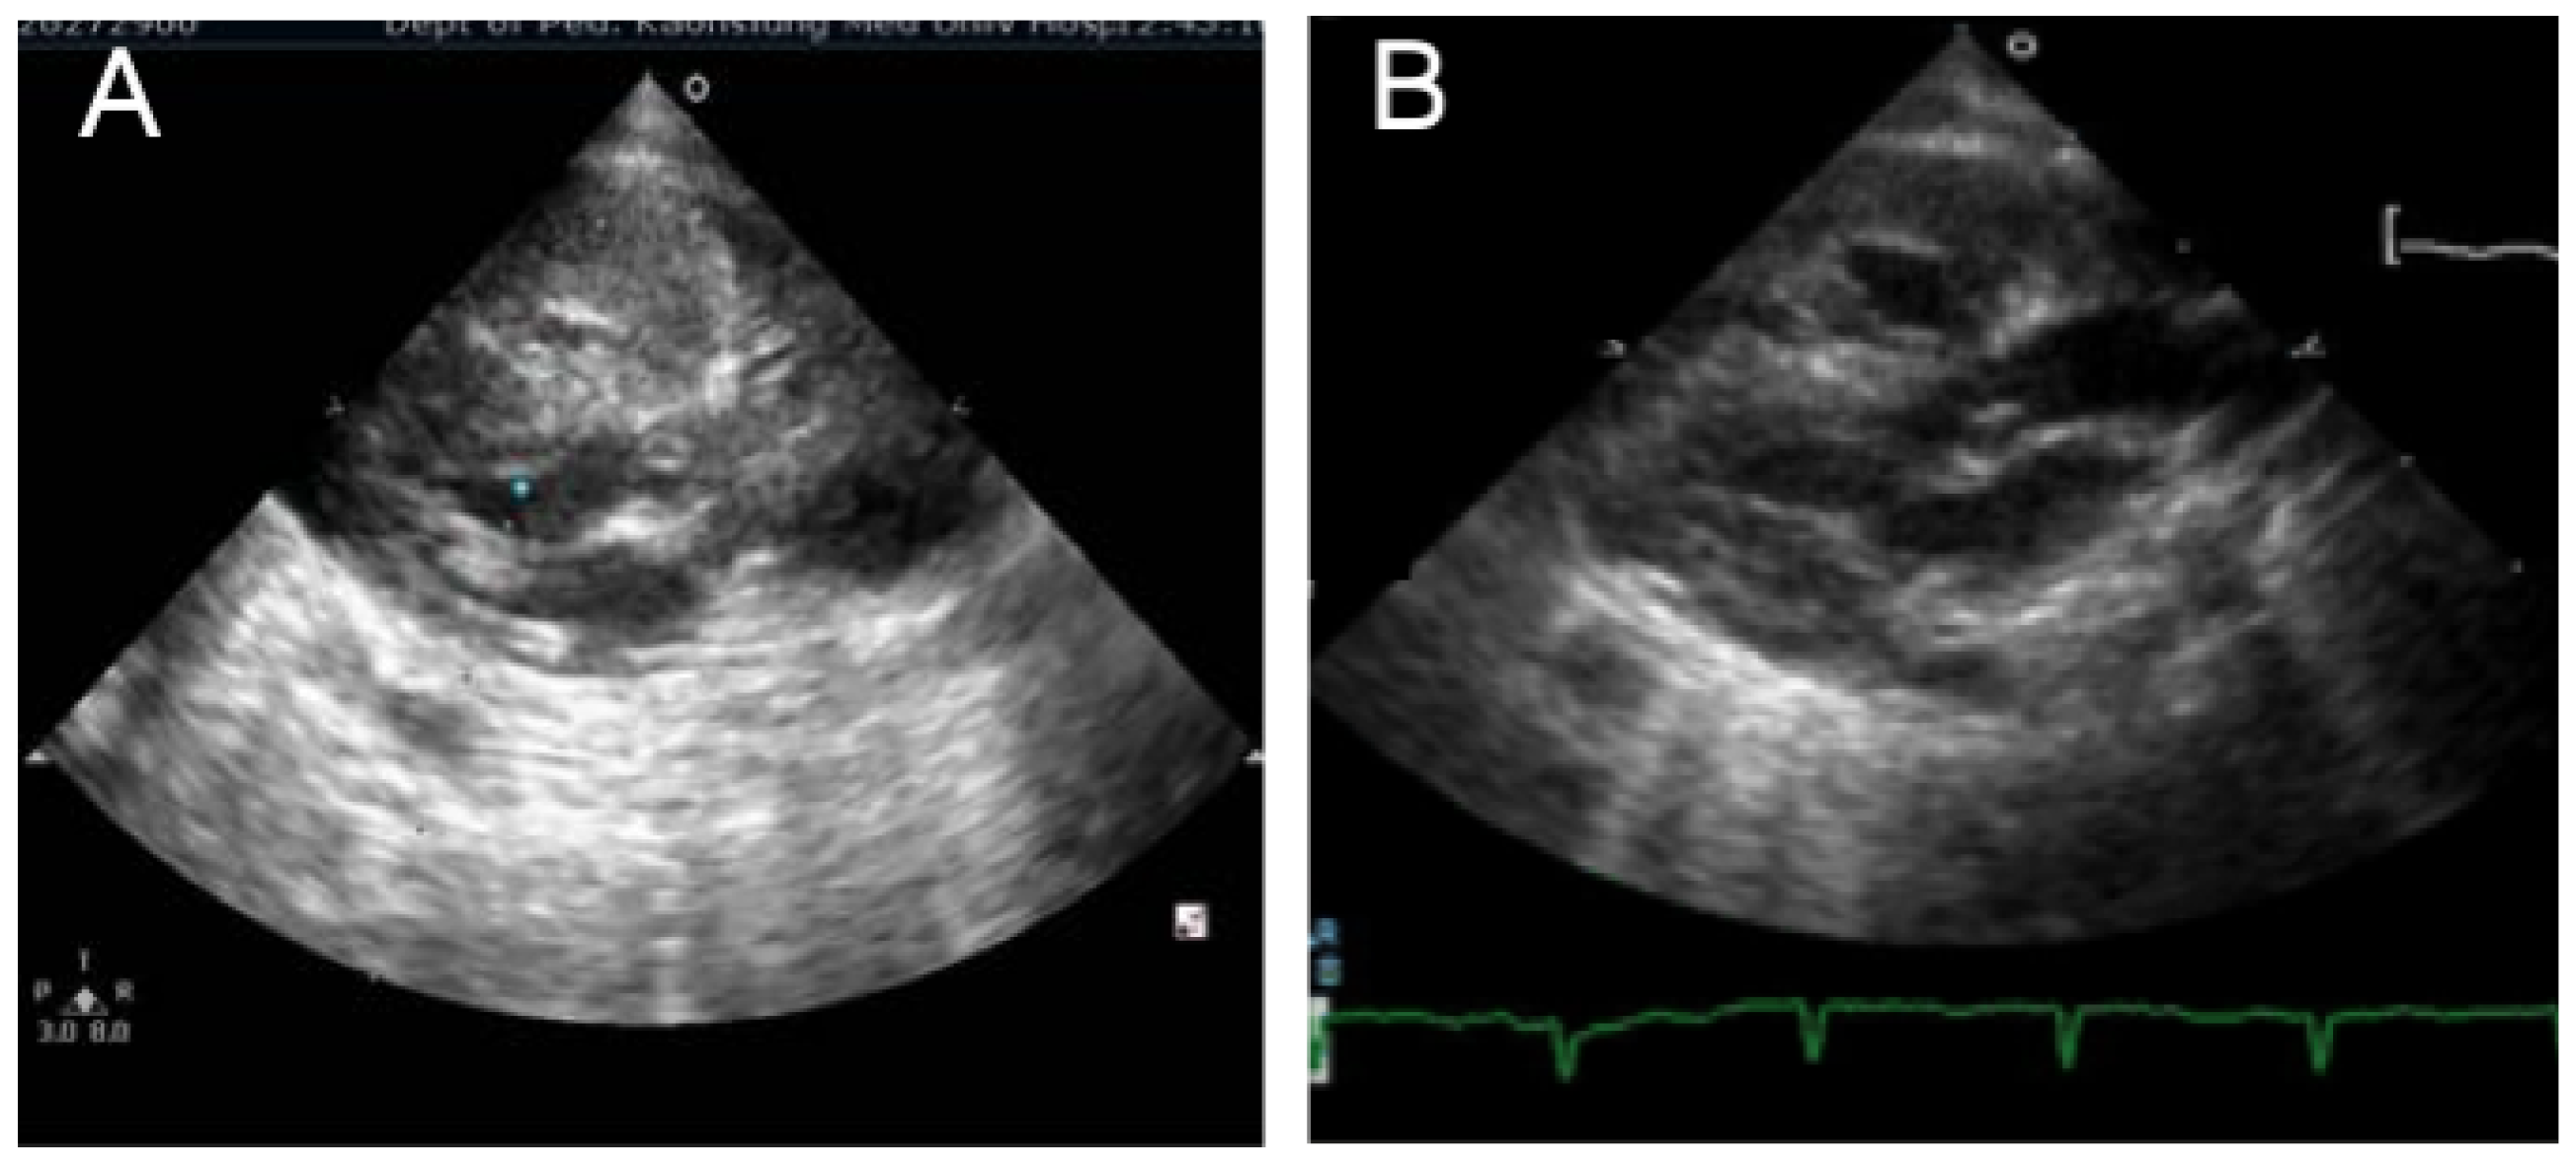

3.7. Case 7